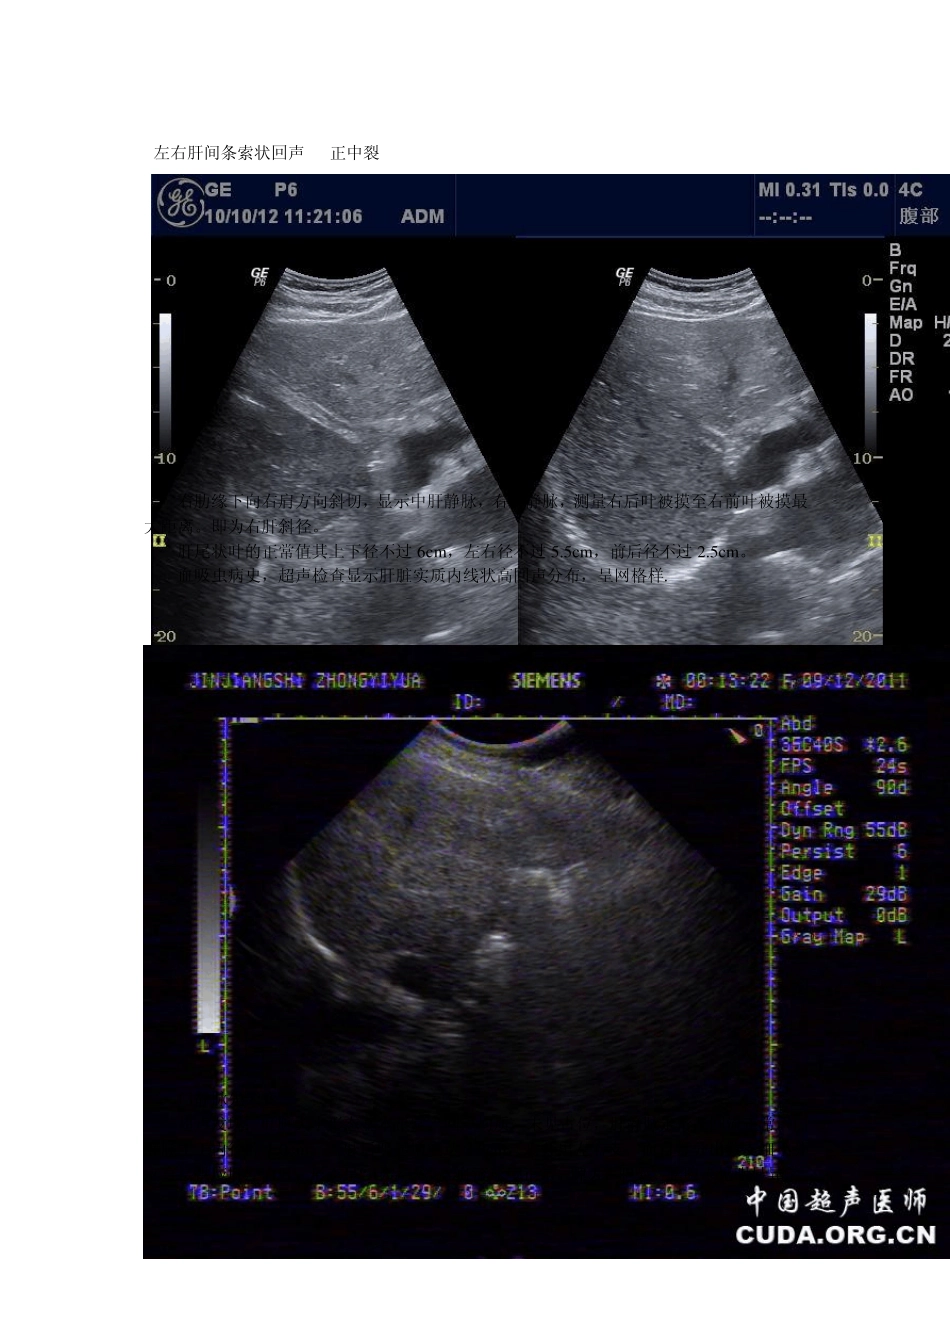

肝脏 1.肝右锁骨中线肋缘下长度:正常人肝脏在平稳呼吸时,超声在肋缘下扫查不到或稍触及。 2.肝右叶最大斜径:12 ~14cm。 3.肝右叶前后径:8 ~10cm。 4.左半肝厚度及长度:分别为5~6cm 、5~9cm。 5.门静脉内径:不超过 1.4cm、血流速度范围:13~25 cm/s、血流量:约 900±217ml/min。 6.肝动脉峰值速度范围:65~85cm/s 、阻力指数:0.6~0.75。 胆囊与胆道 胆囊最大纵切面长径:约 7~9cm 、前后径:多不超过 3cm 胆囊壁厚:2~3mm 左右肝管内径:约 2mm 、总肝管内径:3~4mm 、总胆管内径:6~8mm 胆囊动脉血流峰值速度:45~65cm/s 、阻力指数:0.5~0.67 脂餐一小时后收缩 ≥1/2 肝硬化,肝包膜下迂曲管状回声,范围约 63X31mm,较宽处约 8.1mm,管状暗区旁似可见片状高回声。 B 超于肝右后叶中上段探及大小约 2.8cmx2.5cm 圆形低弱回声包块,囊壁清晰,厚约 0.3cm,呈强回声,周边无晕环,内透声差,后方回声无明显增强,可见侧方声影,CDFI 示:其内无血流信号。其余未发现异常。考虑肝囊肿继发感染,囊壁钙化,CT 确考虑肝脓肿可能. 肝血管瘤,是肝脏的良性肿瘤。以肝海绵状血管瘤最常见。海绵状血管瘤一般是单发的,多发生在肝右叶;约10%左右为多发,可分布在肝一叶或双侧。血管瘤在肝脏表现为暗红,蓝紫色囊样隆起。分叶或结节状,柔软,可压缩,多数与邻近组织分界清楚。病人一般无自觉症状。 B 型超声可检出直径>2cm 的肝血管瘤。典型表现为边界清晰的低回声占位伴有后方不甚明显的回声增强效应。但大多数小血管瘤为强回声,瘤体直径多<5cm,当瘤体较大时,其边界可呈清楚的花瓣状或分叶状,内部有时可见散在的点状低回声和少许纤维束光带。因瘤体回声较肝组织强,内部结构易于辨认,因此诊断符合率高。较大的血管瘤(多>5cm)则表现为内部高低混杂回声,边界不整,形状不一,此为瘤内有纤维性变、血栓形成或坏死所致。有时肝癌也可有类似图像,因此需做其他影像学检查加以鉴别。 左右肝间条索状回声 正中裂 右肋缘下向右肩方向斜切,显示中肝静脉,右肝静脉,测量右后叶被摸至右前叶被摸最大距离。即为右肝斜径。 肝尾状叶的正常值其上下径不过6cm ,左右径不过5.5cm ,前后径不过2.5cm 。 血吸虫病史,超声检查显示肝脏实质内线状高回声分布,呈网格样. 门静脉先天变异 超声发现:肝脏大小形态基本正常,回声均质,未见占位,肝静脉走形及回流正常,门静脉主干内...